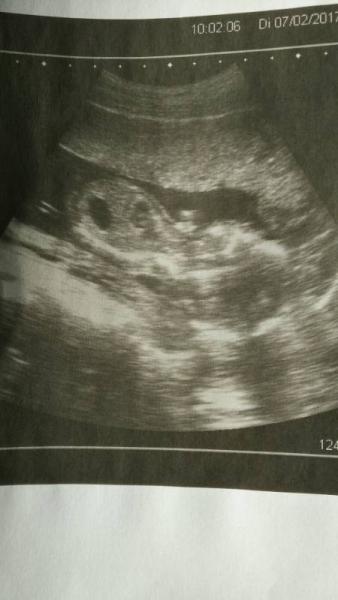

War ja gestern bei meinem Hausarzt und der hat wegen den Bauch und Rückenschmerzen mal die Organe geschallt und oh Wunder oh Wunder wir konnten leider die blase nicht sehen Dafür haben wir beide ein bisschen BabyTV gemacht und schonmal gerätselt was es werden könnte sind aber zu keinem Ergebniss gekommen weil das kleine uns den Rücken und dann die Seite mit angezogenen Beinen gezeigt hat. Als wir fertig waren sagte er dann ich solle mir vorne die letzten drei Bilder ausdrucken lassen. Er ist echt süß. Vielleicht wissen wir am Dienstag was es gibt :)

Bild zu Vorab Ultraschall - Forum für Juli - Mamis